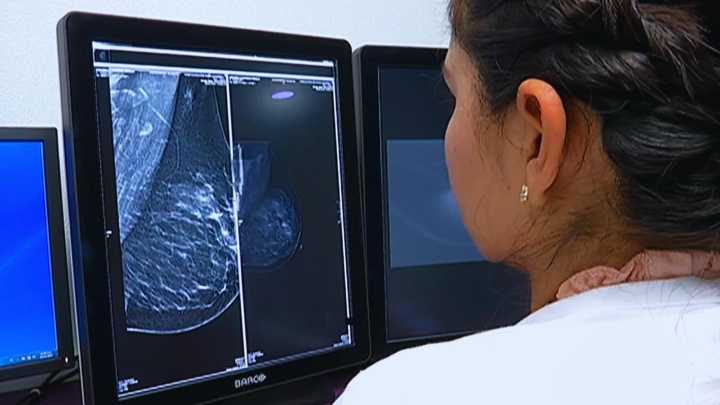

En el marco de la conmemoración del Mes de Sensibilización sobre el Cáncer de Mama , autoridades de salud exhortan a las mujeres a realizarse autoexploraciones y acudir a mastografías , ya que una detección temprana puede salvar vidas.

María Magdalena Mendívil , directora de Salud Reproductiva en Chihuahua, recordó que el cáncer de mama sí tiene cura si se detecta a tiempo .

A veces es una lesión tan pequeña como la que se puede encontrar en una mastografía, explicó.

Indicó que, en ocasiones, la lesión puede ser tratada mediante una incisión mínima o, en otros casos, se toma una biopsia para diagnosticar y dar tratamiento en el mismo procedimiento.